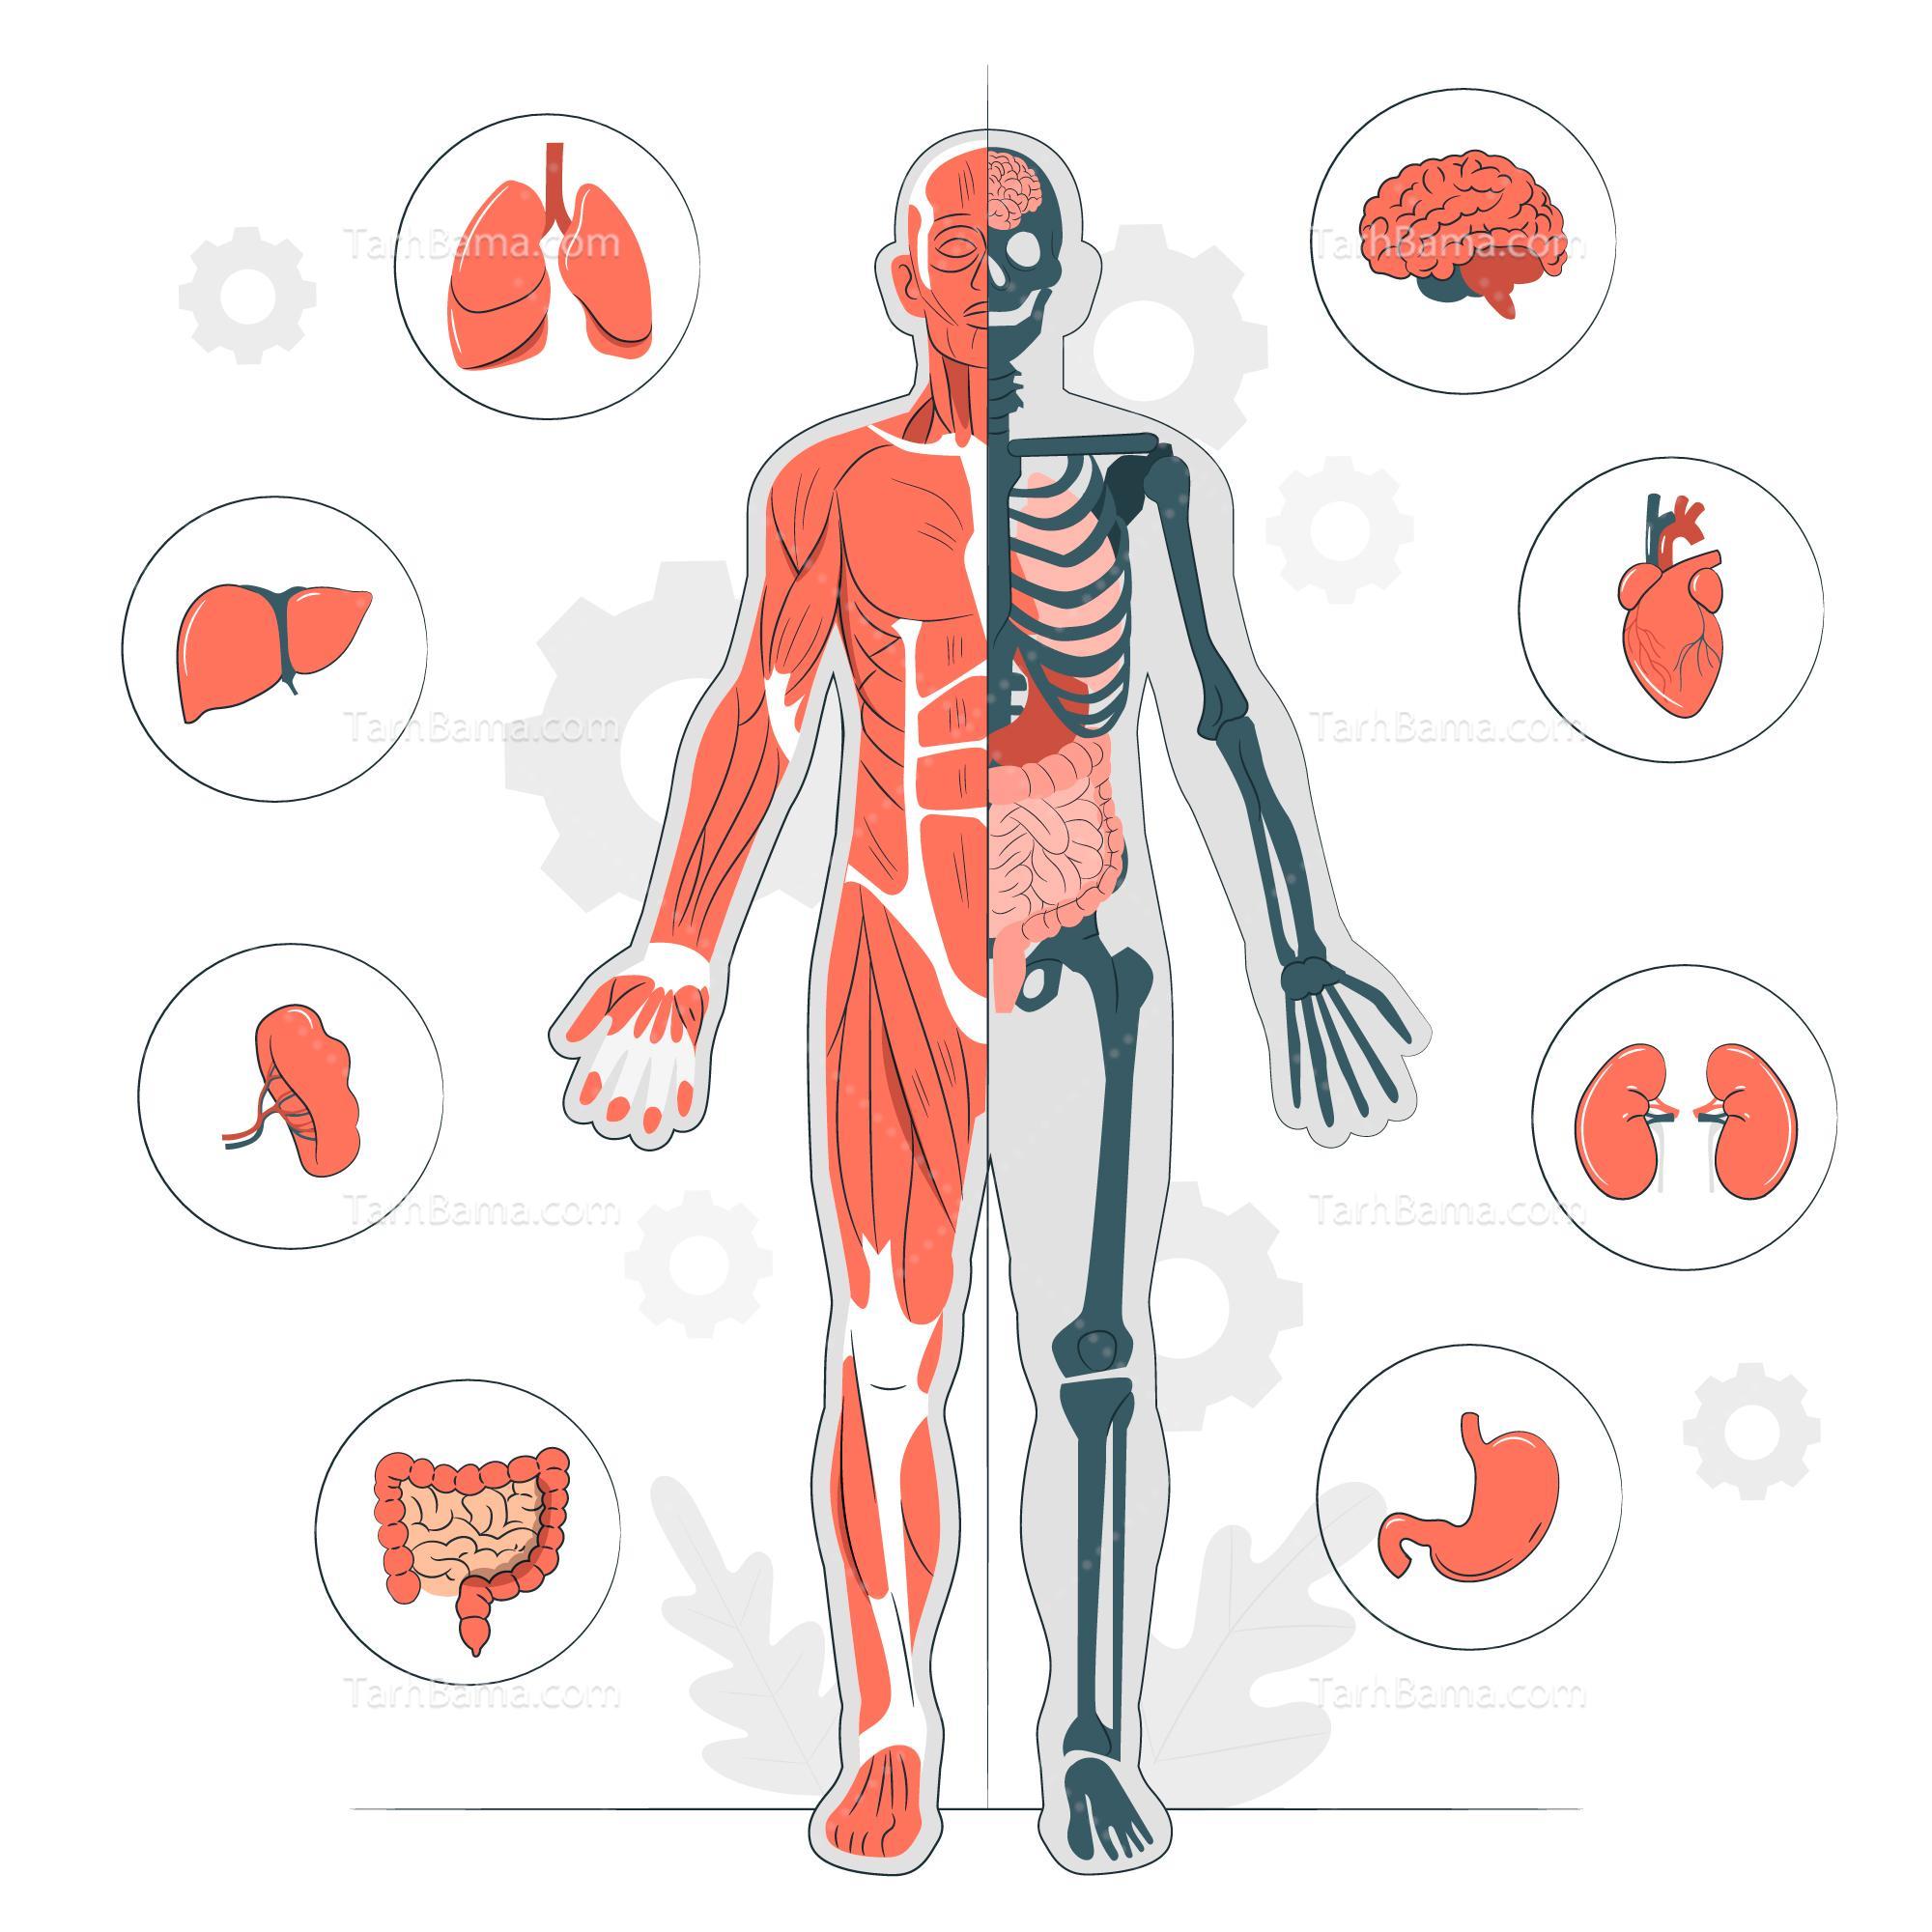

قیمت: 52٬000 تومان - دسته بندی فایل: پاورپوینتپاورپوینت آناتومی بدن انسان

فروش ویژه پاور پوینت حرفه ای بیماری انسدادی مزمن ریه با تخفیف استثنایی فقط 62000 هزار تومان تعداد اسلاید: 26 اسلاید

قیمت: 108٬000 تومان - دسته بندی فایل: پاورپوینتپاورپوینت آشنایی با اناتومی انسان

فروش ویژه پاور پوینت حرفه ای آشنایی با اناتومی انسان ریه با تخفیف استثنایی فقط 124000هزار تومان تعداد اسلاید: 67 اسلاید